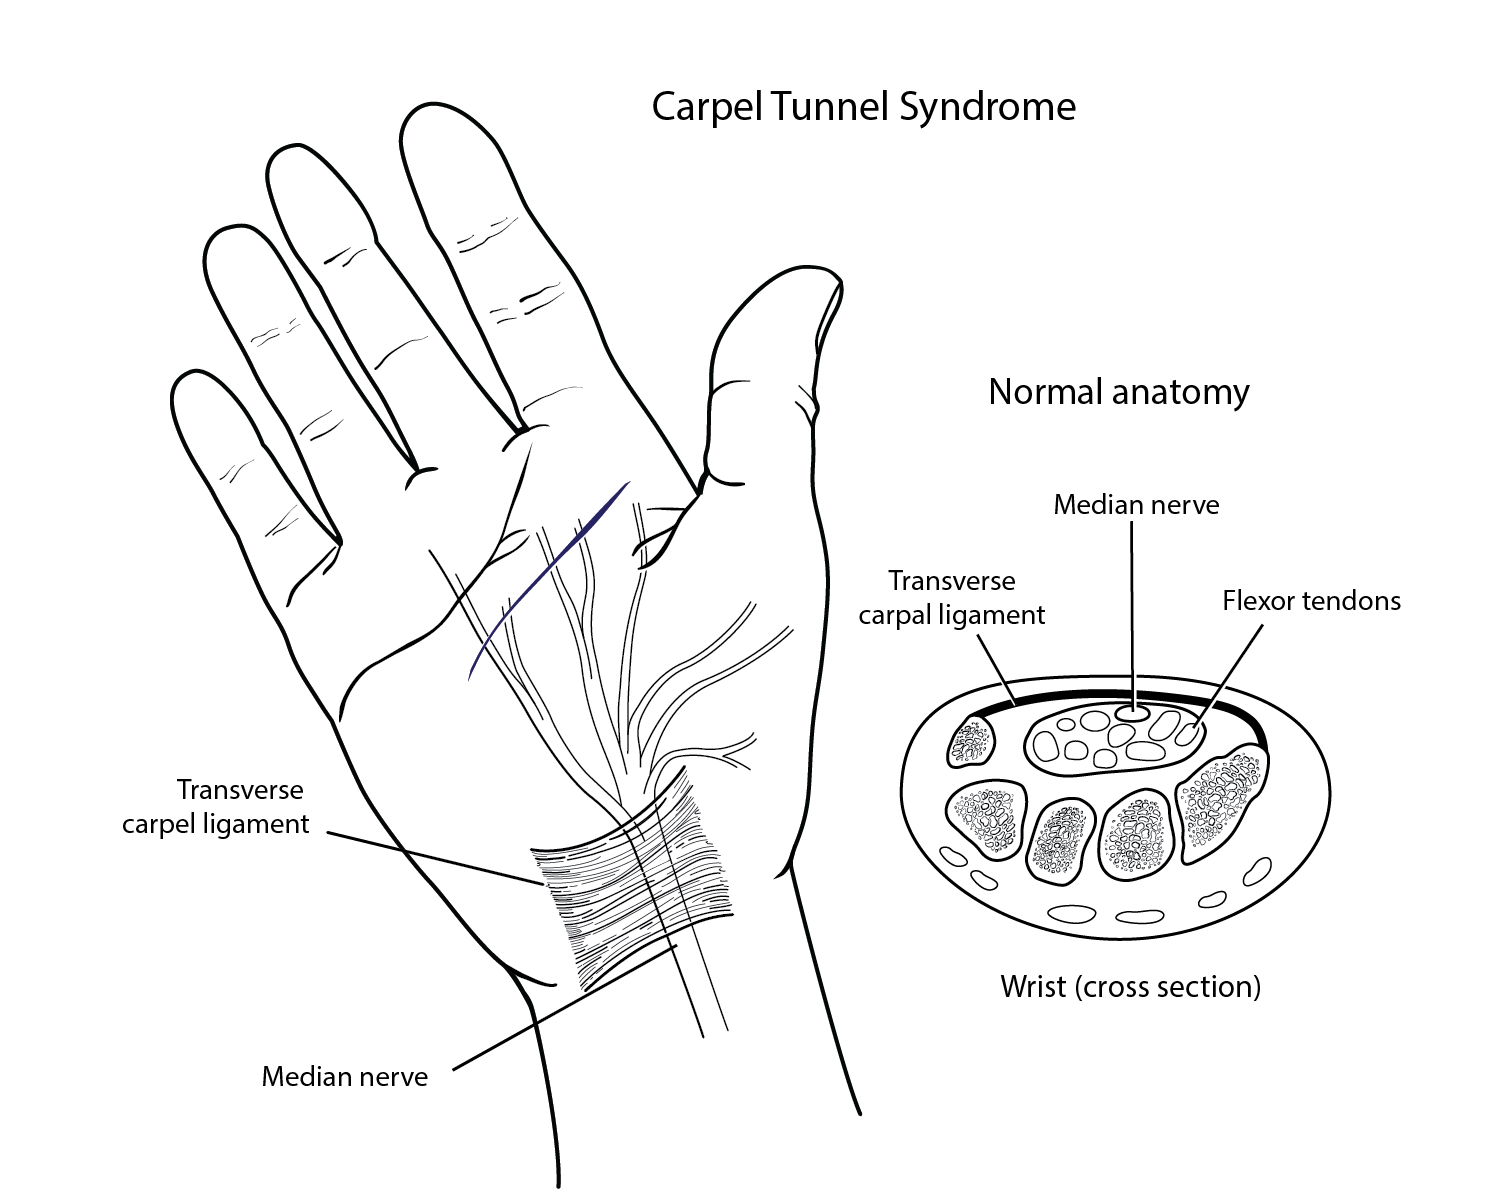

Informative, straightforward illustrations can help patients better understand their medical condition, treatments and procedures. Doctors and healthcare providers can use illustrations to communicate more effectively and reduce a patient’s anxiety about their condition or treatment.

Surgical illustrations visually depict operative techniques, surgical anatomy, and complex procedures. They are created with high anatomical accuracy and serve as a visual bridge between complex surgical knowledge and learners, clinicians, or patients.